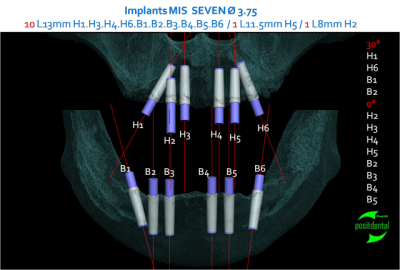

Je réalise l'ensemble, guide chirurgical de forage, positionneur d'implants et armature du provisoire à partir des images native DICON du scanner. Dans ce cas la chirurgie et la mise en fonction de la prothèse transitoire ont été effectuées en une opération.

Pour réaliser ce travail j'ai eut besoin du montage haut et bas sur cire.

1 je confectionne un guide radiologique.

2 après le scanner le patricien garde les planches et m'indique l'emplacement et le choix des implants et m'envoie le CD du dentascan

3 par e-mail je retourne l'étude avec des coupes, mise en situation et densité osseuse qui permettent d'évaluer la fixation primaire et la stratégie du forage

4 le guide, le provisoire, la reconstitution osseuse en stéréo lithographie, le tout fabriqué au labo puis livré avec un délai suffisamment nécessaire avant l'intervention pour être contrôlé physiquement et le guide inox stérilisé.

la réussite chirurgicale de cette intervention revient au Docteur Jean KOSKIEVIC (Paris).

posit